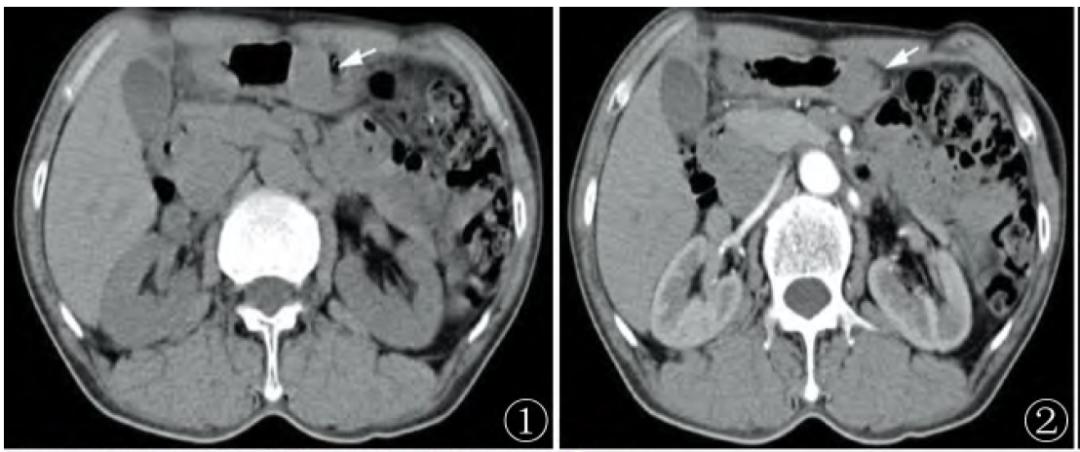

胃血管球瘤影像表现

位置:胃窦部;

大小、形态和质地:均较小,直径多小于 3cm,类圆形或椭圆形,边界清晰, 实性结构的软组织块,且均为实性结构,未见囊性改变;

肿块位于胃黏膜下,实质密度较均匀,平扫约30-40HU,未见坏死及囊变,病灶表面可见溃疡, 病灶内可见小点状钙化;

增强扫描表现:动脉期、门静脉期和延迟期均呈明显强化,动脉期肿块周边可见有结节样强化或均匀强化,门静脉期和延迟期仍有明显强化,强化程度类似于门静脉、下腔静脉,甚至与降主动脉类似;

经典型胃血管球瘤与肝脏海绵状血管瘤强化方式类似,动脉期局部或周边出现絮片状强化,门脉期进一步均匀强化,强化峰值通常出现在门脉期,CT值与同层腹主动脉相近,延迟期持续强化;

血管瘤型胃血管球瘤强化峰值可出现在动脉期,门脉期及延迟期持续均匀强化。